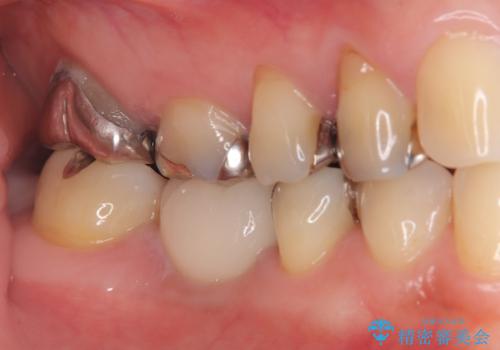

- 右下奥歯が虫歯で被せ物が取れてしまい、また噛めるようにしたいとのことで来院されました。

虫歯が大きく、歯を保存することが難しい状態でしたので、抜歯してインプラント治療を行うこととなりました。